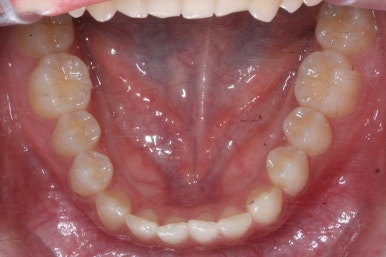

이번 환자분의 경우는 아랫니는 약간 삐뚤함이 있지만 굳이 교정치료를 원하지 않으셨기 때문에 윗니들만 부분교정으로 해결하기로 했습니다.

이상적으로라면 위-아래를 한 쌍으로 해야 교합을 맞추기에 유리하지만 이번의 경우는 윗니만 해도 충분히 교합을 맞출 수 있겠다고 판단하여 부분교정을 하였습니다.

윗니만 하고 싶다고 무조건 윗니 부분교정이 가능한 것이 아니기 때문에 반드시 교정전문의와의 상의를 추천드립니다.

아래치아는 여전히, 당연히 장치가 붙지 않은 채로 그대로 둡니다.